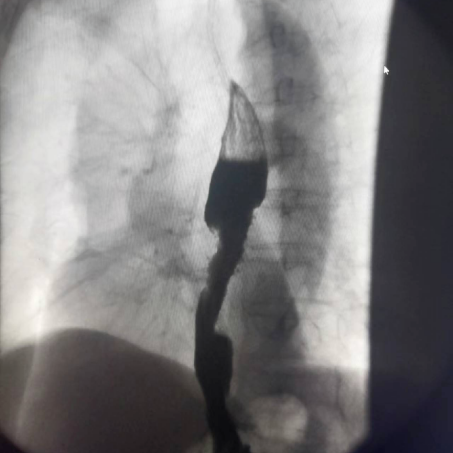

ERCP

造影显示效果,借助内窥镜进行ERCP操作,是一种微创的肝内胆管取石的治疗方式。

是胆道术后T管引流患者的常规检查方法,可以了解术后胆道内有无残留结石、胆道狭窄及Oddi括约肌的畅通情况。